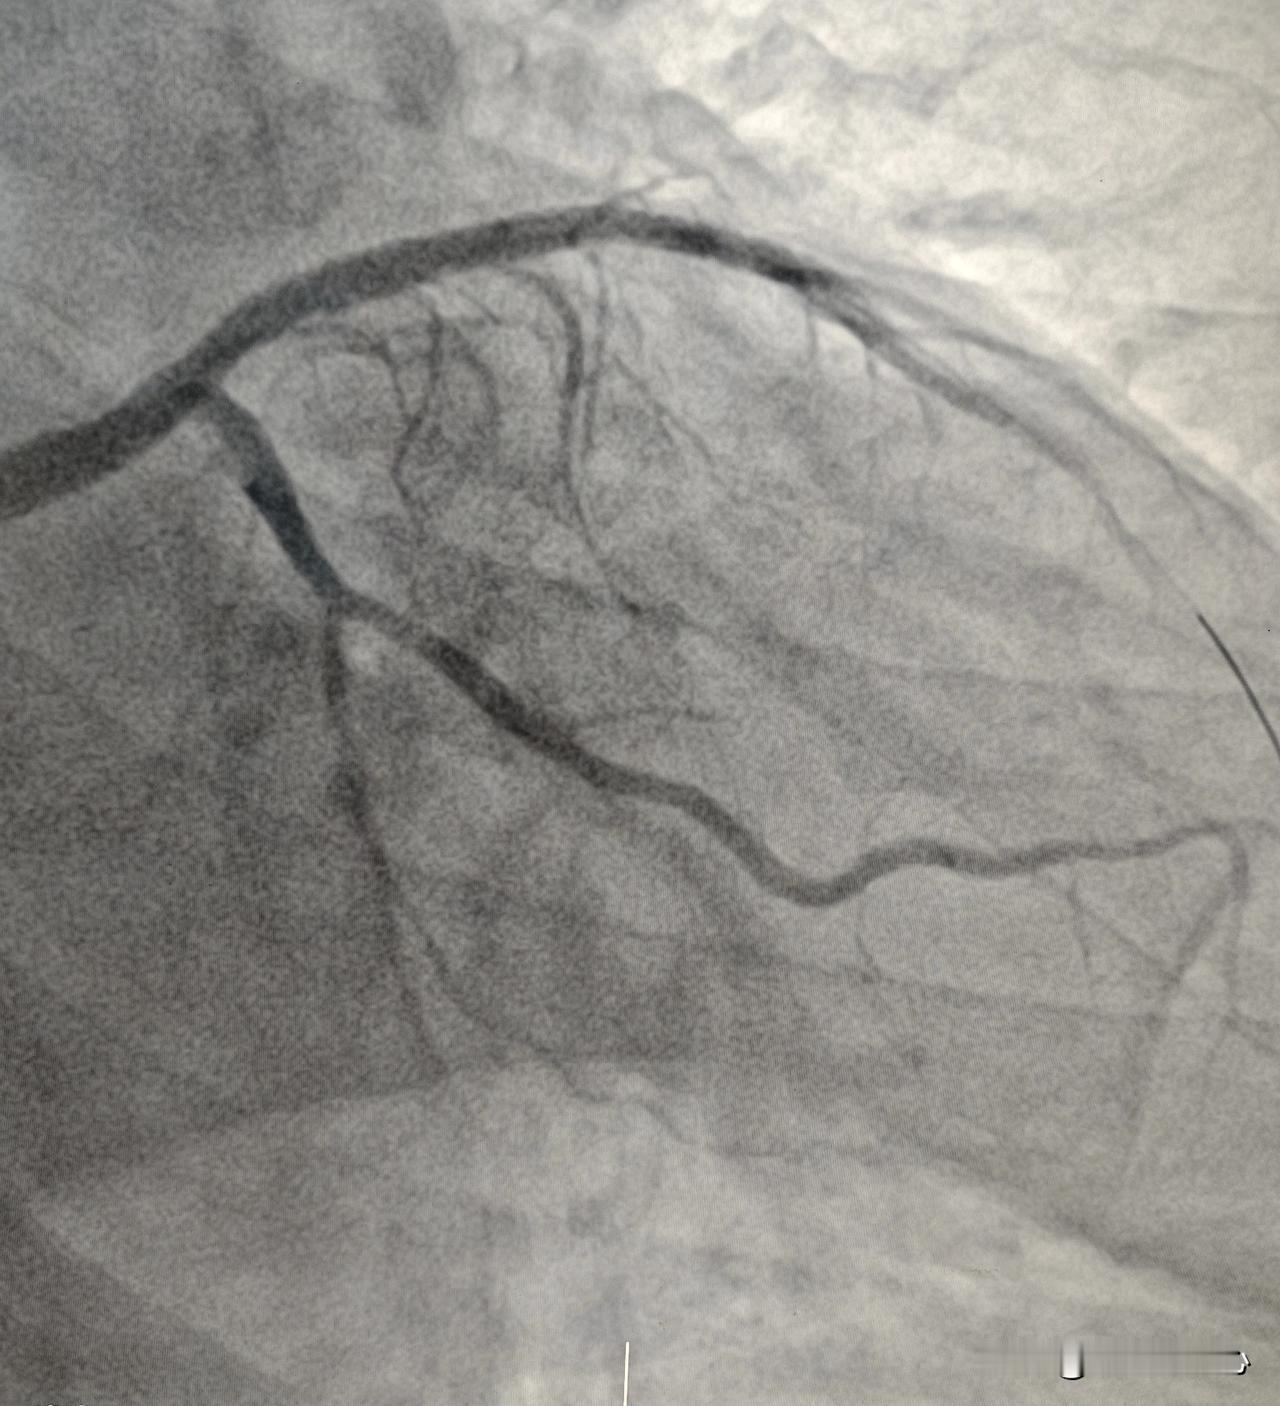

32岁男性患者,心衰,射血分数27%,前降支狭窄50%,把前降支做支架能改善心衰

同一段病变血管放2个支架还是3个支架好?今天上午和病人术前谈话,根据冠脉造影的情